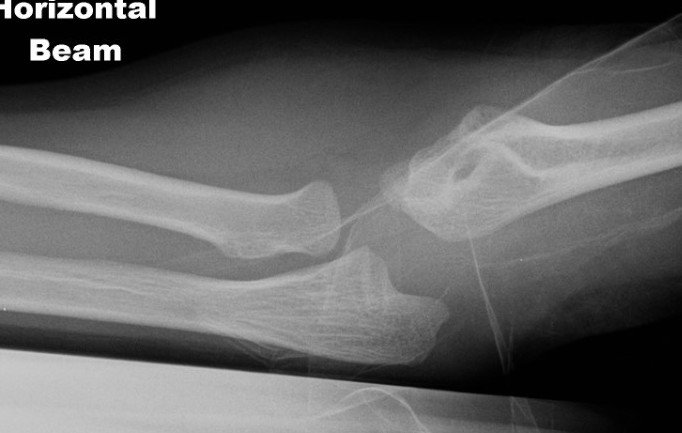

Internal oblique xray

Edmonds et al J Paediatr Orthop 2021

- 140 cases lateral condyle fracture treated non operatively

- displacement < 1.2 mm on internal oblique had failure rate of 58%

- displacement > 1.2 mm on internal oblique had failure rate of 1%

Kurtulmus et al Eur J Orthop Surg Traumatol 2014

- 27 patients with < 2 mm displacement on AP view

- 16 found to have > 2 mm displacement on subsequent internal oblique view